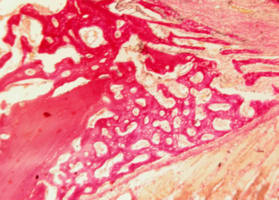

В толще соединительной ткани определяется интенсивное костеобразование – видны тонкие вновь образованные балки молодой костной ткани, окрашенные более интенсивно, чем интактная кость.

В них определяется резко повышенная клеточность - число клеток (остеобластов) на единицу площади по сравнению с прилежащей зрелой костной тканью нижней челюсти, что подтверждает интенсивность клеточного размножения и пролиферации.

Идет активное новообразование капилляров микроциркуляторного русла, обеспечивающее интенсивное кровоснабжение регенерата (рис. 4).

Рис. 4. Нижняя челюсть кролика через 14 суток после остеопластики слева, смесь лиофилизированной аллоспонгиозы и ГАП 1:1.

Синими стрелками обозначены тонкие новообразованные костные балки, содержащие множество активных остеобластов, указанных черными стрелками.

Зелеными стрелками показаны вновь образованные тонкостенные капилляры.

Окраска - пикрофуксин по ван Гизон, х400.